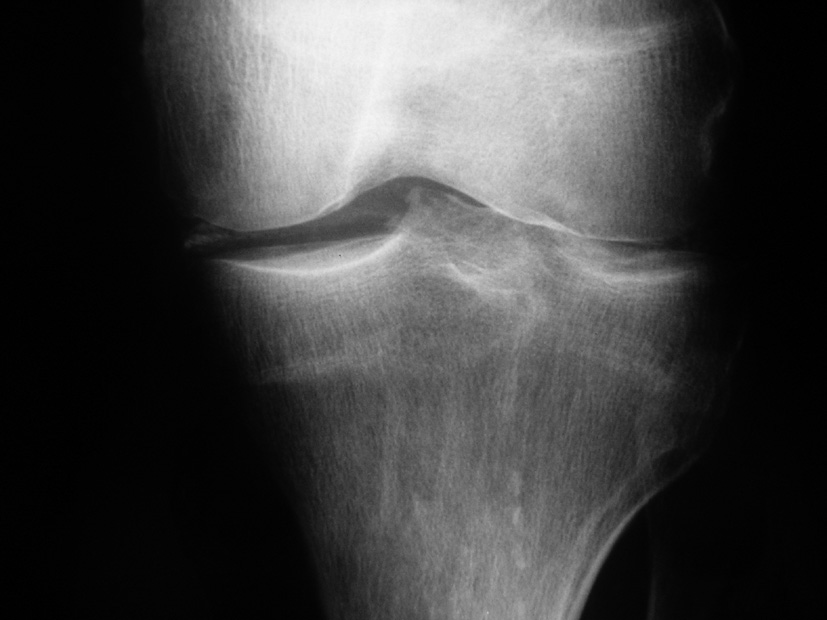

Dans ses antécédents, vous notez une arthrite du genou droit il y a un an — elle vous apporte une radiographie de cette époque —, une hypertension artérielle traitée par Nifédipine, une appendicectomie.